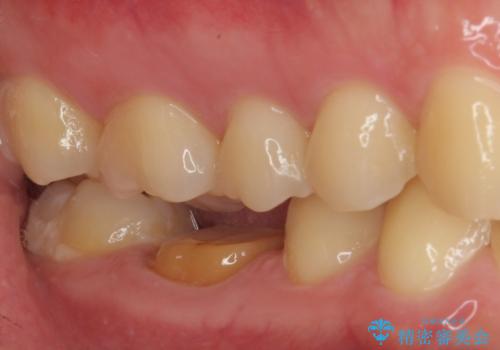

- 銀歯を白くしたいとのことで来院された患者様です。

拡大鏡視野下にて、銀歯を外して、虫歯を除去して、オールセラミッククラウンに適した形に削りました。